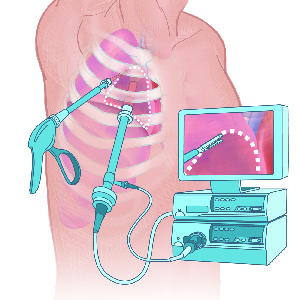

Detailreiche Fotografien aus der medizinischen Praxis ergänzen die Texte; moderne, genaue,

wissenschaftliche Zeichnungen geben Einblick in die Anatomie und die Funktion der Lunge und

anderer Organe.